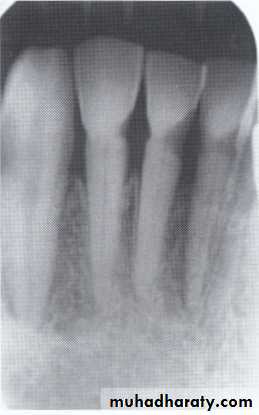

Radiographically:

Bulbous crownsCervical constriction

Thin roots

Early obliteration of roots canals & pulp chambers.

Radiographically (Type I& II ):

partial or total obliteration of pulp chambers & root canals by continued formation of dentin.

roots may be short & blunted.

Normal cementum, periodontal membrane & bone .